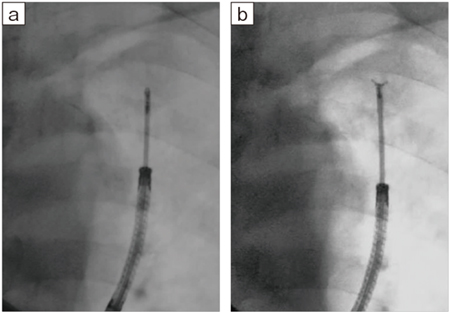

図12 Accent適用症例画像2:各透視線量モードにおける病変とデバイスの視認性の向上

a:Normalモード(3.4mGy/min) b:Midモード(2.1mGy/min) c:Lowモード(1.2mGy/min)

より低線量の透視線量モード(Lowモード)でも視認性が向上しており、病変の位置確認をしながらブラシを視認できる。